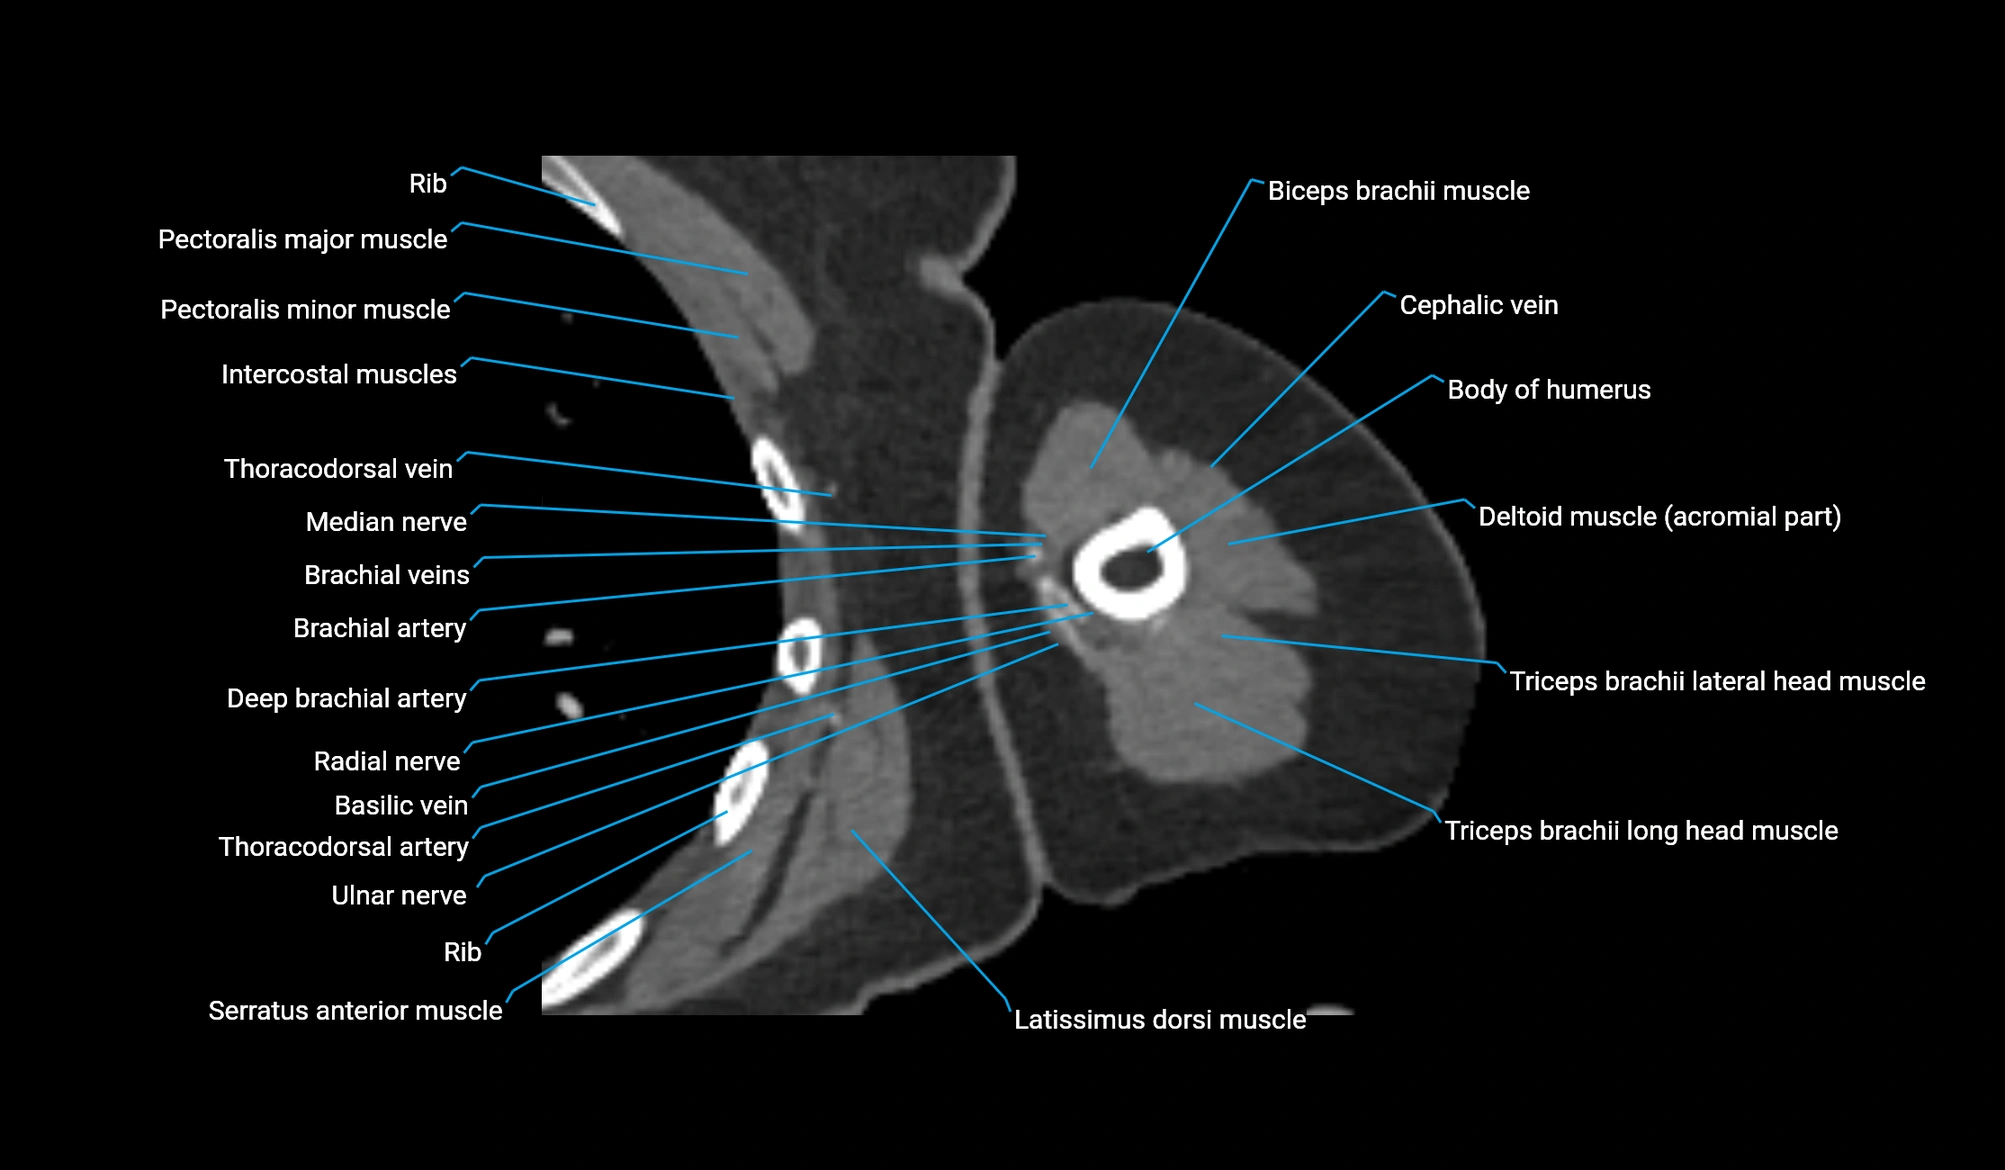

CT image